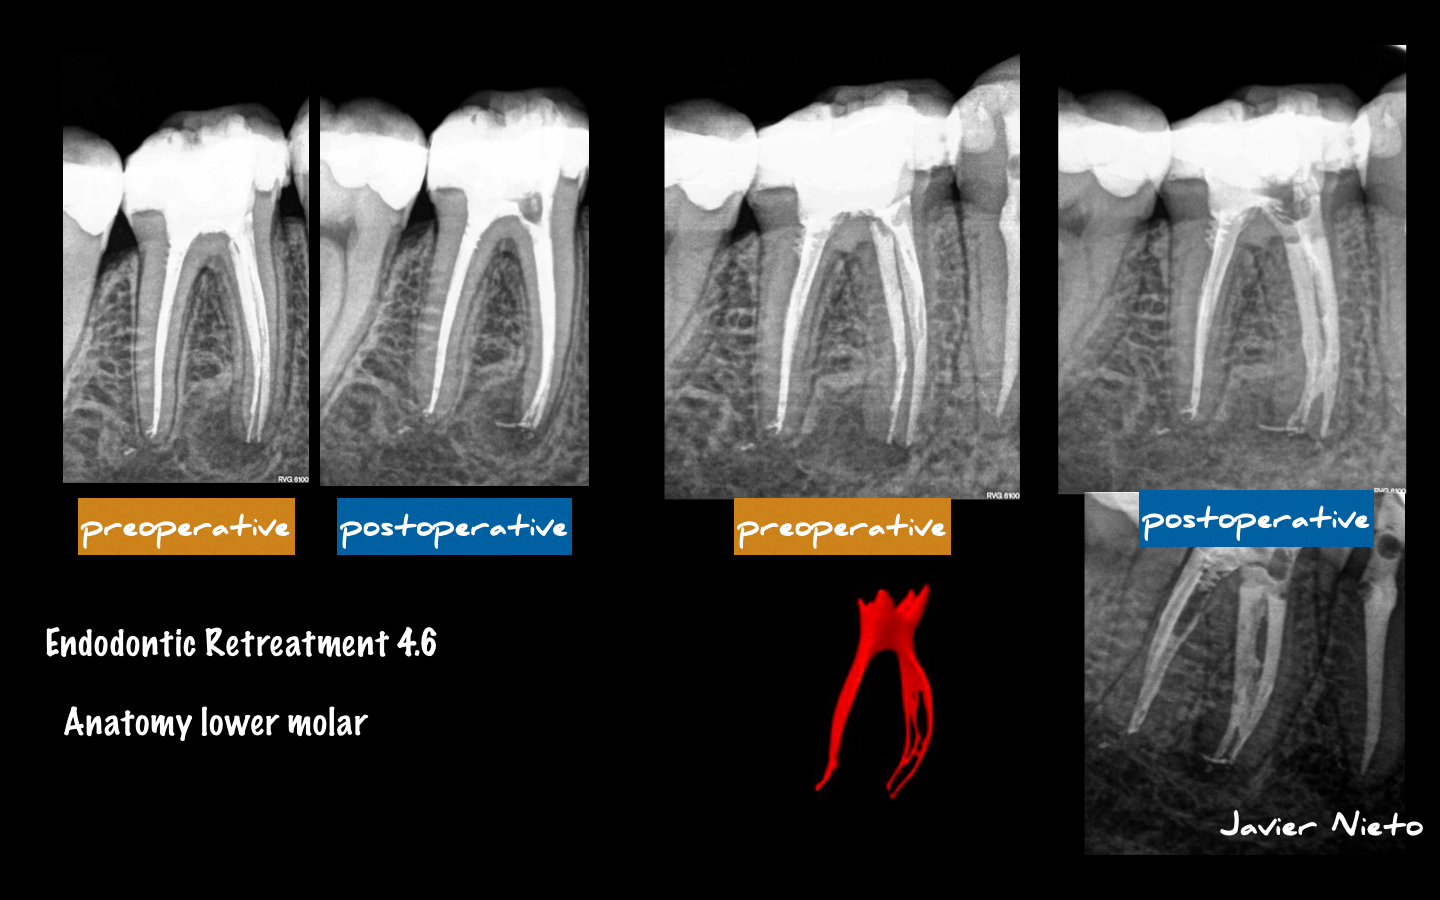

Retratamiento de un 4.6

Paciente que acude a nuestra consulta para valorar un tratamiento de endodoncia realizado hace 6 meses, motivo, quieren exodonciarlo (EXTRAERLO) ya que según el operador, «hay veces que la endodoncia fracasa» .

Evaluamos el caso y decidimos retrartarlo, ya que pensamos que existe una subobturación.

Como conocemos la gran variabilidad anatómica de las raíces mesiales de los molares inferiores, sospechamos del itsmo de unión.

Nuestro empeño irá encaminado a limpiar ese istmo.

Finalmente, un caso con muy buen pronóstico.